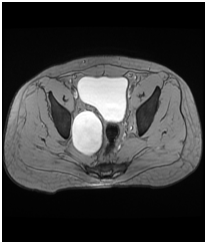

30 years old gentleman arrived with complaints of lower abdominal discomfort for 6 months with vague right iliac pain with normal gut and bladder habits. He experienced no other co-morbidities. Clinical examination findings were normal. Blood investigation was done within normal limits. Ultrasound abdomen showed a complex cyst with internal echoes and absence of vascularity in the right side of the pelvis. Contrast CT abdomen revealed non enhancing unilocular cystic mass on the right lateral pelvic wall.MRI, abdomen with gadolinium revealed T1 hypotenuse, T2/STIR heterointense enhancement within the lesion. Colonoscopy was normal. He underwent laparotomy under general anesthesia, through Pfannenstiel extra peritoneal approach mass lesion of size 8cm x 6 cm identified in the right pelvic region in the course of obturator nerve producing the compression over the lateral wall of the bladder without any infiltration of the bladder and bowel. It was arising from the nerve bundle, the lesion was well capsulated. It was highly vascular with blood supply from the branches of internal iliac arteries. The feeding arterial branch was ligated, outer capsule opened and an inner mass removed completely after leaving the capsule intact in view of nerve injury. Haemostasis achieved, postoperative period was uneventful. Histopathology revealed a mass of size 8x6.5x3.5cm section shows unencapsulated lesion comprised of spindle cells with wavy nuclei prominent myxoid stroma and scant collagen, conclusive of as Neurofibroma (Figures 1-4).

Figure 2&3 MRI, abdomen with gadolinium revealed T1 hypotenuse, T2/STIR heterointense enhancement within the lesion.